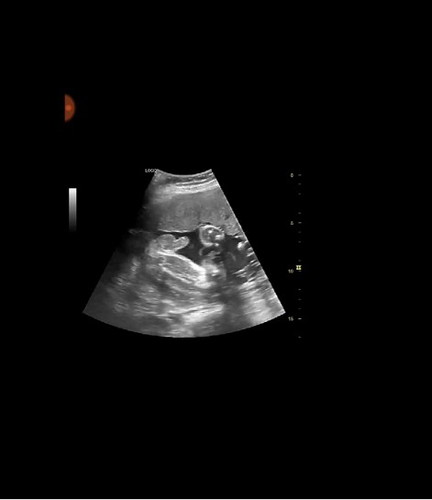

Hye, mommy². Boleh kongsi cerita tak? 1. Siapa kat sini pernah ectopic? 2. Siapa kat sini rahim terbalik? Sekadar kongsi² cerita kehidupan. Saya pernah berkahwin dengan cinta pertama saya, hubungan 7 tahun lebih . Disahkan mengandung akan tetapi kandungan saya luar rahim dipanggil ectopic. Dan scan rahim saya terbalik (retroverted uterus) . Dipendekan cerita, bekas suami memaki hamun saya tak dpt bg zuriat. ( Dokter dah cakap peluang saya nak hamil sangat tipis dan risiko ectopic mungkin akan berulang lagi dan lebih sakit ) Bekas suami sanggup tinggalkan saya dan berkahwin baru dengan wanita yg sudah ada anak satu. Dan hasil perkahwinan yang saya dengar bekas suami dikurniakan dua anak perempuan. Selepas itu,ada la seorang lelaki ni nak tackle saya tak dpt²,sebab jual mahal katakan. Sebab lelaki ni kenal kwn² saya dan korek² rahsia saya dari kwn². Setahun setengah adalah dia menunggu,hujung² saya jadi isteri dia la pula. Sebab menjalani hubungan rmh tangga kedua sy takut nak kahwin sbb takut suami kedua tidak dapat terima kekurangan saya. Kerana dasar Cinta... Saya dah bagitau kat suami yg sekarang ni, jikalau saya tidak mengandung pada hujung tahun 2019 ,kita berpisah. Jatuh air mata suami saya cakap cam tu,suami pulak marah kat sy . Bukan apa kan risau dia malu yg sy betul² tidak dpt memberi zuriat. Suami cakap kita berdoa jangan putus asa, Tuhan pasti akan memberi. Pada May 2019 , saya tidak datang haid. Awal check Urine Pregnancy Test,bertapa terkejutnya saya melihat 2 garisan ( POSITIF ) kena check awal kalau lambat haid takut ectopic lagi, Dokter dah bagi peringatan. Doa suami dan saya seperti mimpi, saya disahkan hamil. Gembiranya dalam hati .... Dan sekarang usia kandungan masuk 8 bulan, due date bulan January 2020 . ??? Baby boy lagitu... Bertapa bahagianya saya dan suami.